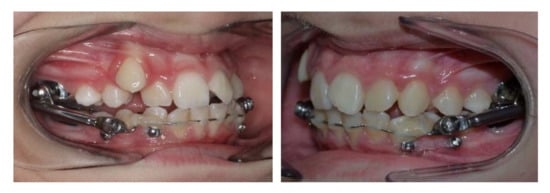

A 11-year-old patient presented to the private practice with her parents with a chief complaint of an unattractive smile, mainly due to an upper canine. The facial analysis showed an hypodivergent facial type with a reduced lower-third of the face, a convex profile with mandibular retrusion and upper lip protrusion with a proper nasolabial angle (Figure 1). The mini-esthetic analysis showed a superior inter-incisive line not coinciding with the median of the face, migrated on the left side, a ratio between arch amplitude and amplitude of the smile in the norm, and a reduced exposure of the smile with an irregular and asymmetrical smile arc. The intraoral clinical analysis revealed sagittal relationships of molar class II and canine class II, an upper interincisive line migrated on the left side, decreased transversal development of the upper arch, a severe crowding in the upper arch with a lack of space for 1.3 alignment, a 6.5 mm overjet, a 3.5 mm overbite, and an increased Spee curve (Figure 1 and Figure 2). The patient asked for treatment because the upper right canine (UR3) was not aligned and ectopic in the upper arch. Panoramic radiography and lateral cephalogram were required to confirm the diagnostic hypothesis of class II malocclusion and to measure incisors proclination. The cephalometric analysis showed a skeletal class II, hypodivergence and proclination of the upper and lower incisors (Figure 3, Table 1 and Table 2).

Figure 2.

Pretreatment models.

Figure 4.

Herbst appliance reinforced with an Hybrid Hyrax Expander and two miniscrews in the lower arch.